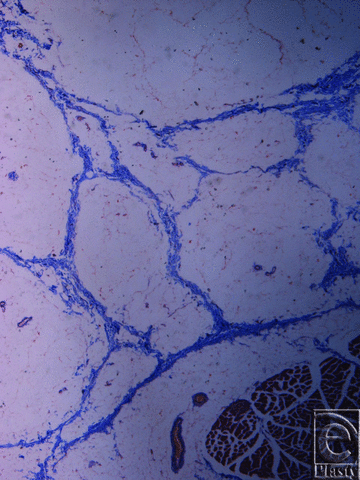

![]() |

| Figure 4. Inframammary crease. Masson trichrome stain ×25. The collagen fibers originate from the muscle fascia and continue their course in the fibrocollagen bundles in a beehive pattern. |